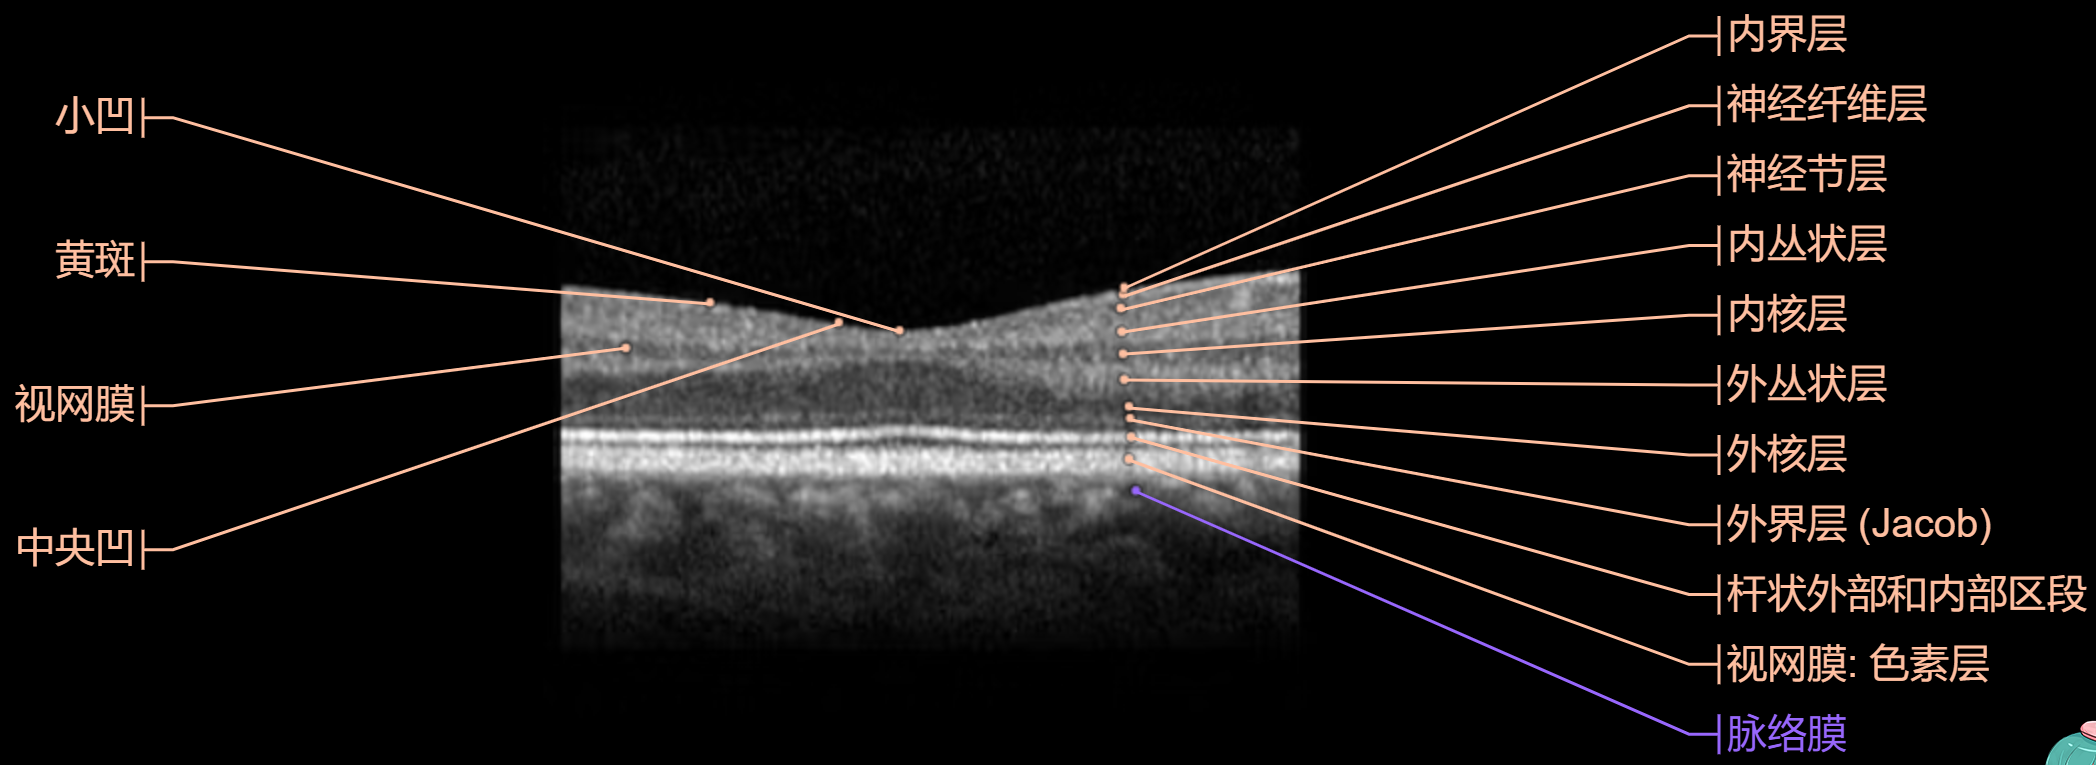

- 光学相干断层扫描(OCT)

OCT 图:

OCT (Optical Coherence Tomography):

- 用途:OCT是一种非侵入性成像测试,可以生成眼睛内部结构,特别是视网膜的高分辨率横截面图像。

- 优点:OCT对于检测视网膜疾病(如黄斑变性、黄斑水肿、视网膜裂孔)及其管理至关重要,因为它提供了细胞层级的结构细节。